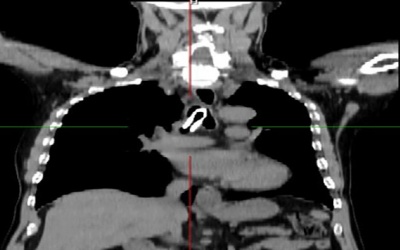

Chỉ trong một tuần trở lại đây, Bệnh viện Việt Đức tiếp nhận tới 10 ca động mạch chủ, trong đó có 3 ca lóc động mạch chủ type A cấp tính – một trong những nguyên nhân chính gây ra...